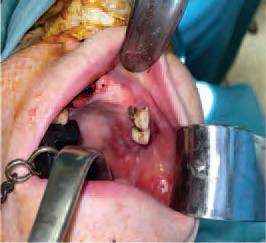

The zygomatic implant perforated (ZIP) flap for rehabilitation of patients with midfacial oncology defects: a report of three cases B. Martin, E. Cotter, C. Bowe, J.E. O’Connell

145 CLINICAL FEATURE

This edition also includes a peer-reviewed case report on zygomatic implant perforated flaps for patients with midfacial oncology defects by Dr Brian Martin et al., and in our clinical feature, Drs Marchini and Ettinger look at the very pertinent issue of maximising dental attendance in our older population.